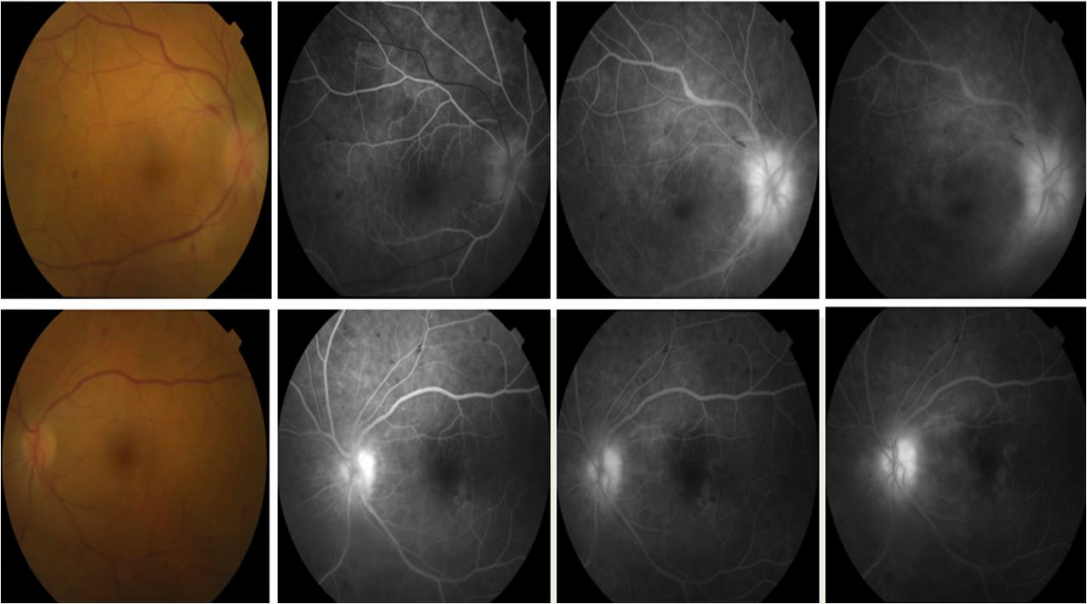

Male, 65-year-old, went to the emergency room complaining of decreased visual acuity bilaterally for 3 weeks, associated with bilateral hypoacusis, vertigo, dysequilibrium, holocranial headache predominantly occipital and frequent episodes of dysphagia for liquids, decreased strength in the right upper limb and limitation of neck mobility for 4 months prior to evaluation. The ophthalmological examination showed isochoric and reactive pupils, visual acuity of 2/10 RE and 6/10 LE, inflammation in the anterior chamber bilaterally (tyndall ++; some fine precipitates), vitritis, edema of the optic nerve head (RE>LE) and multiple retinal haemorrhages (Figure 1 [Fig. 1]). The neurological examination revealed posterior cervical contracture with limitation of extension, normal muscular tone, discrete right hemiparesis of brachial predominance, right osteotendinous hyperreflexia with cutaneous plantar reflex in flexion bilaterally, normal pain and proprioceptive sensitivity, coordination tests without changes, unstable gait with imbalance in turns and absence of meningeal signs.

Figure 1 : Initial retinography and angiography (RE and LE)